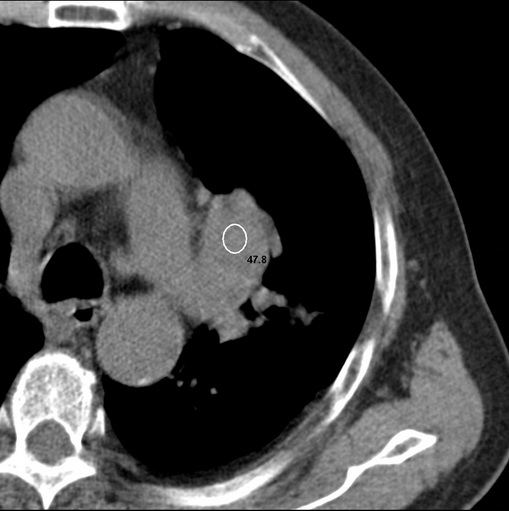

标题: CT25434:胸部CT增强扫描

男性患者 81岁 咳嗽 咳痰 咯血

强化较典型,左上肺癌并纵膈淋巴结转移;左上肺结核并空洞形成;胸膜增厚.

肿块贴近左肺门,包绕左上肺动脉,形态不规则。肿块增强扫描中度强化。纵膈内主动脉弓左旁间隙、气管隆突前、下间隙见多枚淋巴结影。综上考虑左侧中央型肺癌可能性大。图片没有完整上传,尤其是左肺上叶支气管分支层面没有上传,因此不好判断是叶支气管中断还是段支气管中断。另外,下图红色部分所示是“黏液支气管征”吗?